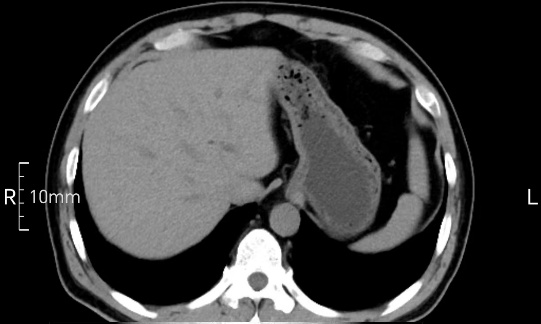

看看下面三幅便知遵醫(yī)囑的重要性。

沒禁食,胃內(nèi)全是食物,導(dǎo)致胃壁顯示不清。

禁食但檢查前沒有喝飽,胃未能漲開,胃壁觀察效果不佳。

完美禁食且喝飽飽,胃壁完美展現(xiàn)。

CT檢查前的“禁食”和“喝飽”,看似矛盾,實則合情合理,分工合作:空腹:是為了讓上腹部(肝膽胰脾腎等)的圖像清晰無干擾,并保障檢查安全。喝水:有效的充盈胃部和、腸道使圖像清晰呈現(xiàn)。兩者巧妙配合,都是為了給您一個最精準(zhǔn)的診斷結(jié)果。